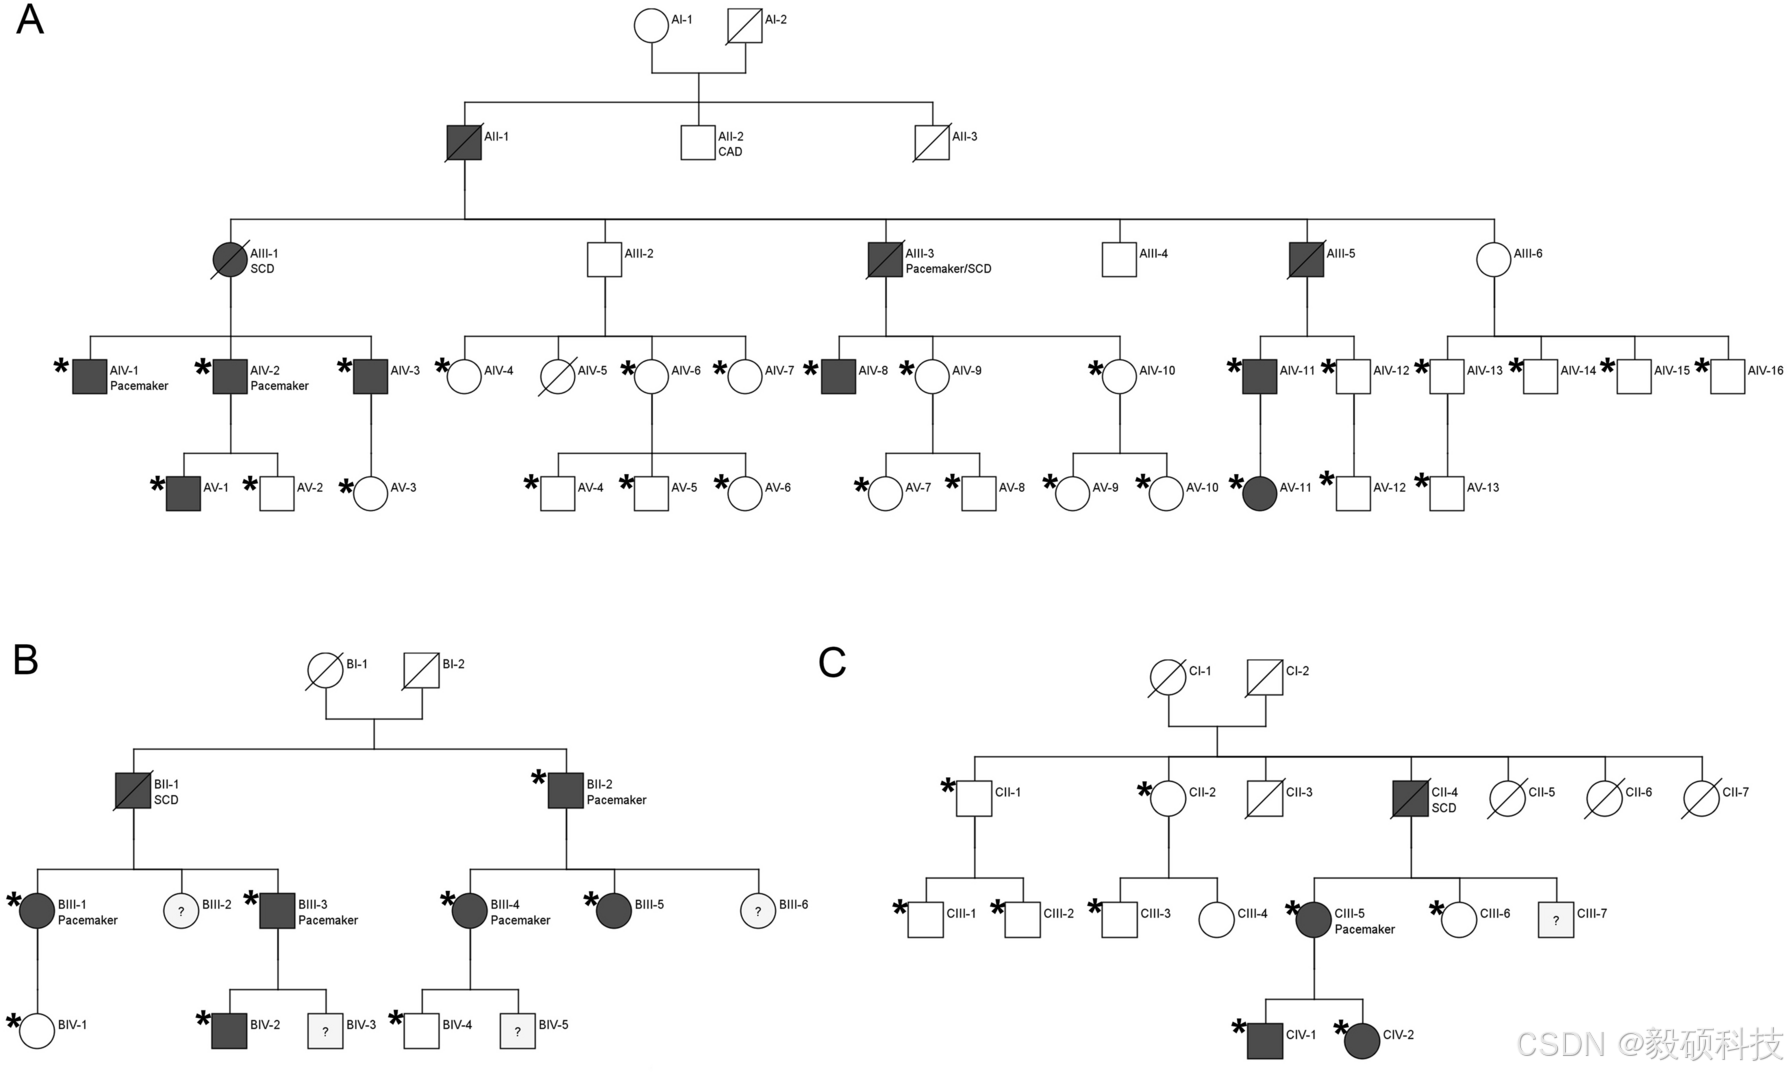

研究组使用 Amrita HCM 的 22 例 PRKAG2 心肌病患者的形态学表现和临床病程,这些患者分属三个无血缘关系的家族。家庭 A(FGD0128)、家庭 B(FGD0137)和家庭 C(FGD0314 )。

图3 该队列研究的三个家庭的详细血统